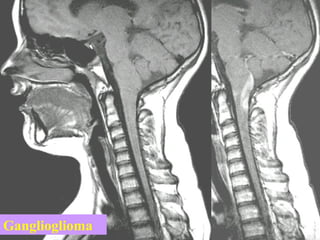

Ganglioglioma